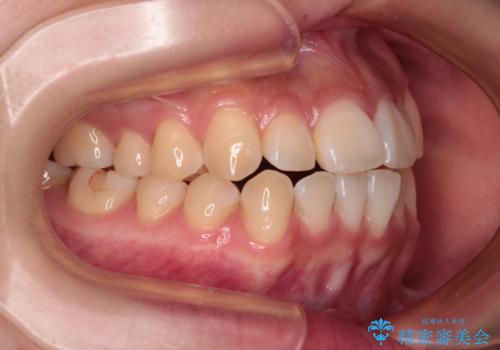

- 口元の突出感と上下前歯のズレを気にして来院された患者様です。

上下左右の第一小臼歯4本を抜歯し、ワイヤー装置にて矯正治療を行うこととしました。

舌のトレーニングをしっかりと行ってくださり、1年半という非常に短い期間で仕上げることができました。